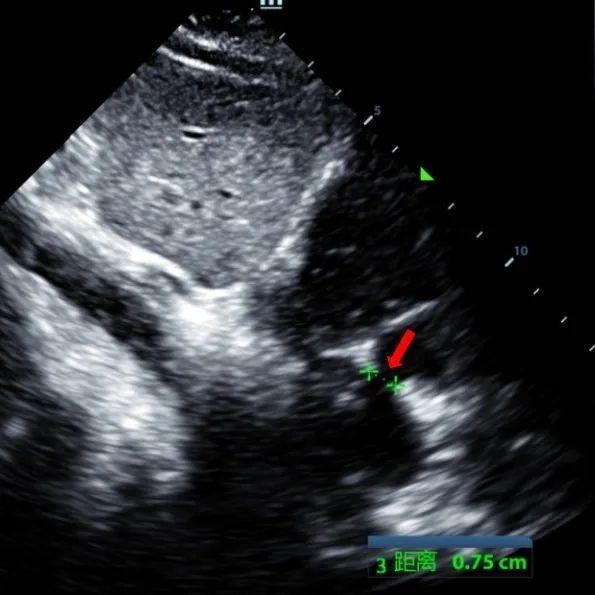

Un garçon de 9 ans avec un TSA secundum (7,5-7,9mm) a été traité à l'aide d'un occulteur MemoSorb BDASD-I 12mm et d'un système d'administration 12F. Aucune complication ou comorbidités n'a été notée avant l'intervention.

Serial echocardiographic follow-ups showed stable device position and favorable cardiac remodeling. Gradual degradation confirmed the occluder's long-term safety and efficacy.